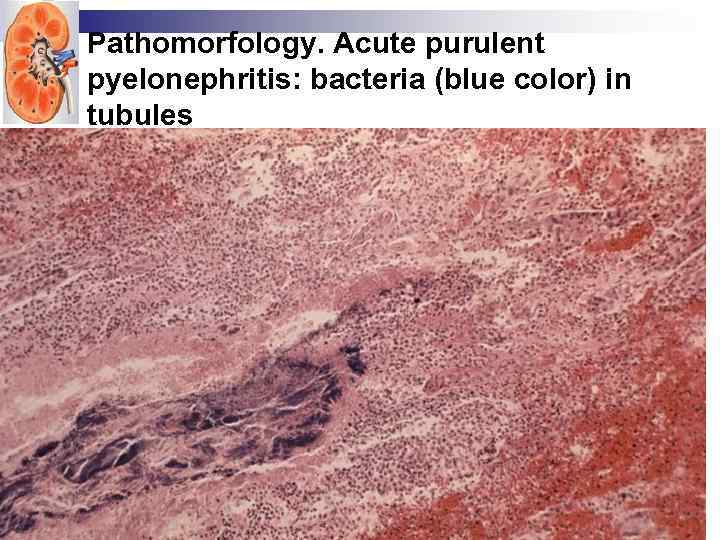

Pathomorfology. Acute purulent pyelonephritis: bacteria (blue color) in tubules

Pathomorfology. Acute purulent pyelonephritis: bacteria (blue color) in tubules